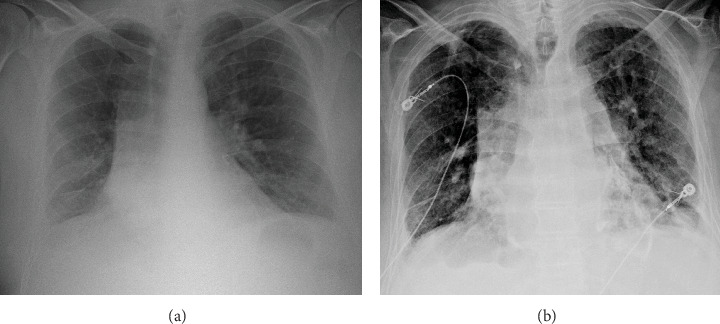

Despite advances in imaging and diagnostics, calcific constrictive pericarditis (CCP) remains a rare and challenging entity, often masquerading as other cardiopulmonary conditions, leading to delayed diagnosis. We present a 70-year-old male with a history of heart failure, atrial fibrillation (AF), cirrhosis, chronic obstructive pulmonary disease (COPD), and prior pleural effusion, who was admitted with acute hypoxic respiratory failure and AF with rapid ventricular response (RVR). Imaging revealed extensive pericardial calcifications, leading to a diagnosis of CCP. The patient's clinical course was marked by refractory hypotension, altered mental status, and progressive cardiohepatic syndrome. Given his high surgical risk, he was managed conservatively and transitioned to palliative care. This case underscores the diagnostic and therapeutic challenges of CCP, particularly in patients with complex comorbidities where surgical intervention is not feasible. It highlights the need for early recognition and individualized management strategies to optimize outcomes in this challenging subset of patients.

Abstract Image